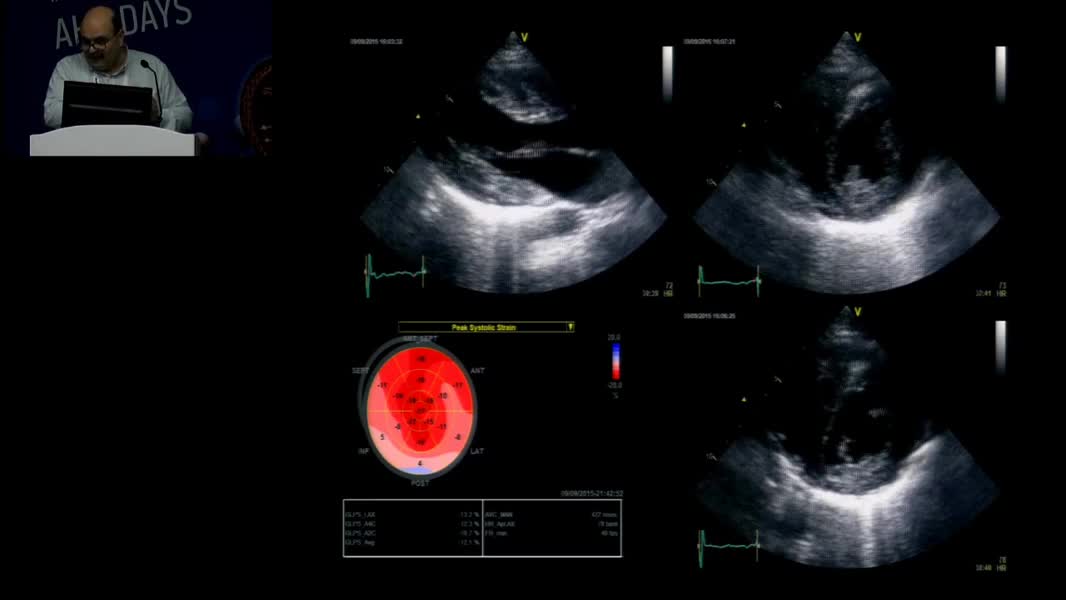

Echocardiographic Face Of Rare Cardiomyopathy And Fabry: Hands On Practical Echocardiography Course In The Diagnosis Of Fabry Disease And Cardiomyopathy Omaç Tüfekçioğlu (TR)

Nadir Miyokardiyopati ve Fabry’nin Ekokardiyografik Yüzü